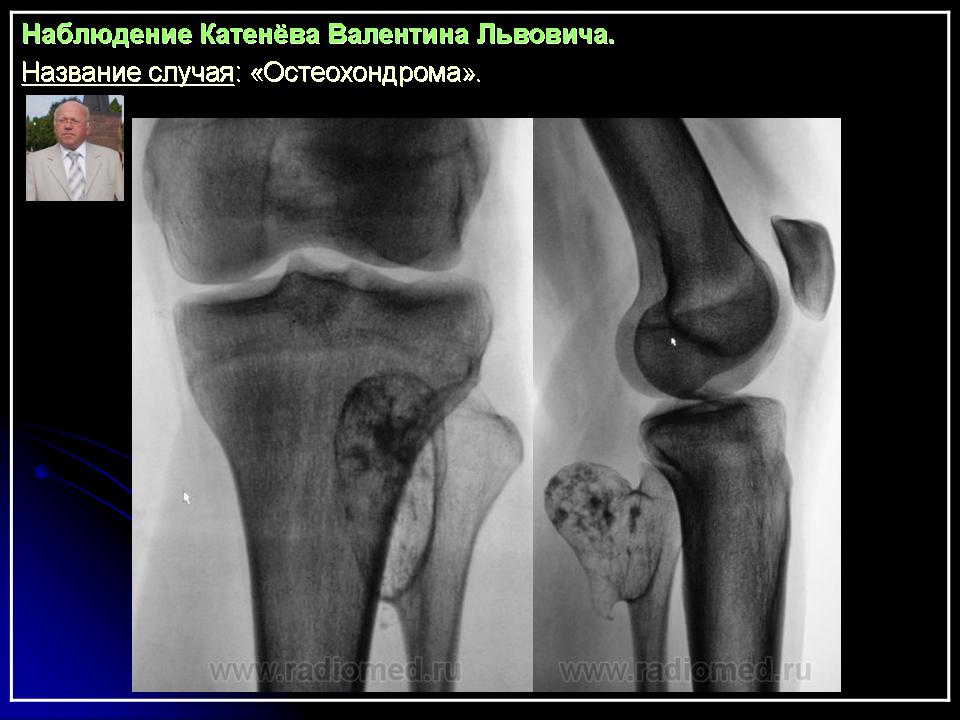

Наблюдение Катенёва В.Л.

Приложения:

1.201607190013.jpg2.201607190017.jpg3.201607190018.jpg4.201607190016.jpg5.201607190019.jpg6.201607190020.jpg7.201607190021.jpg